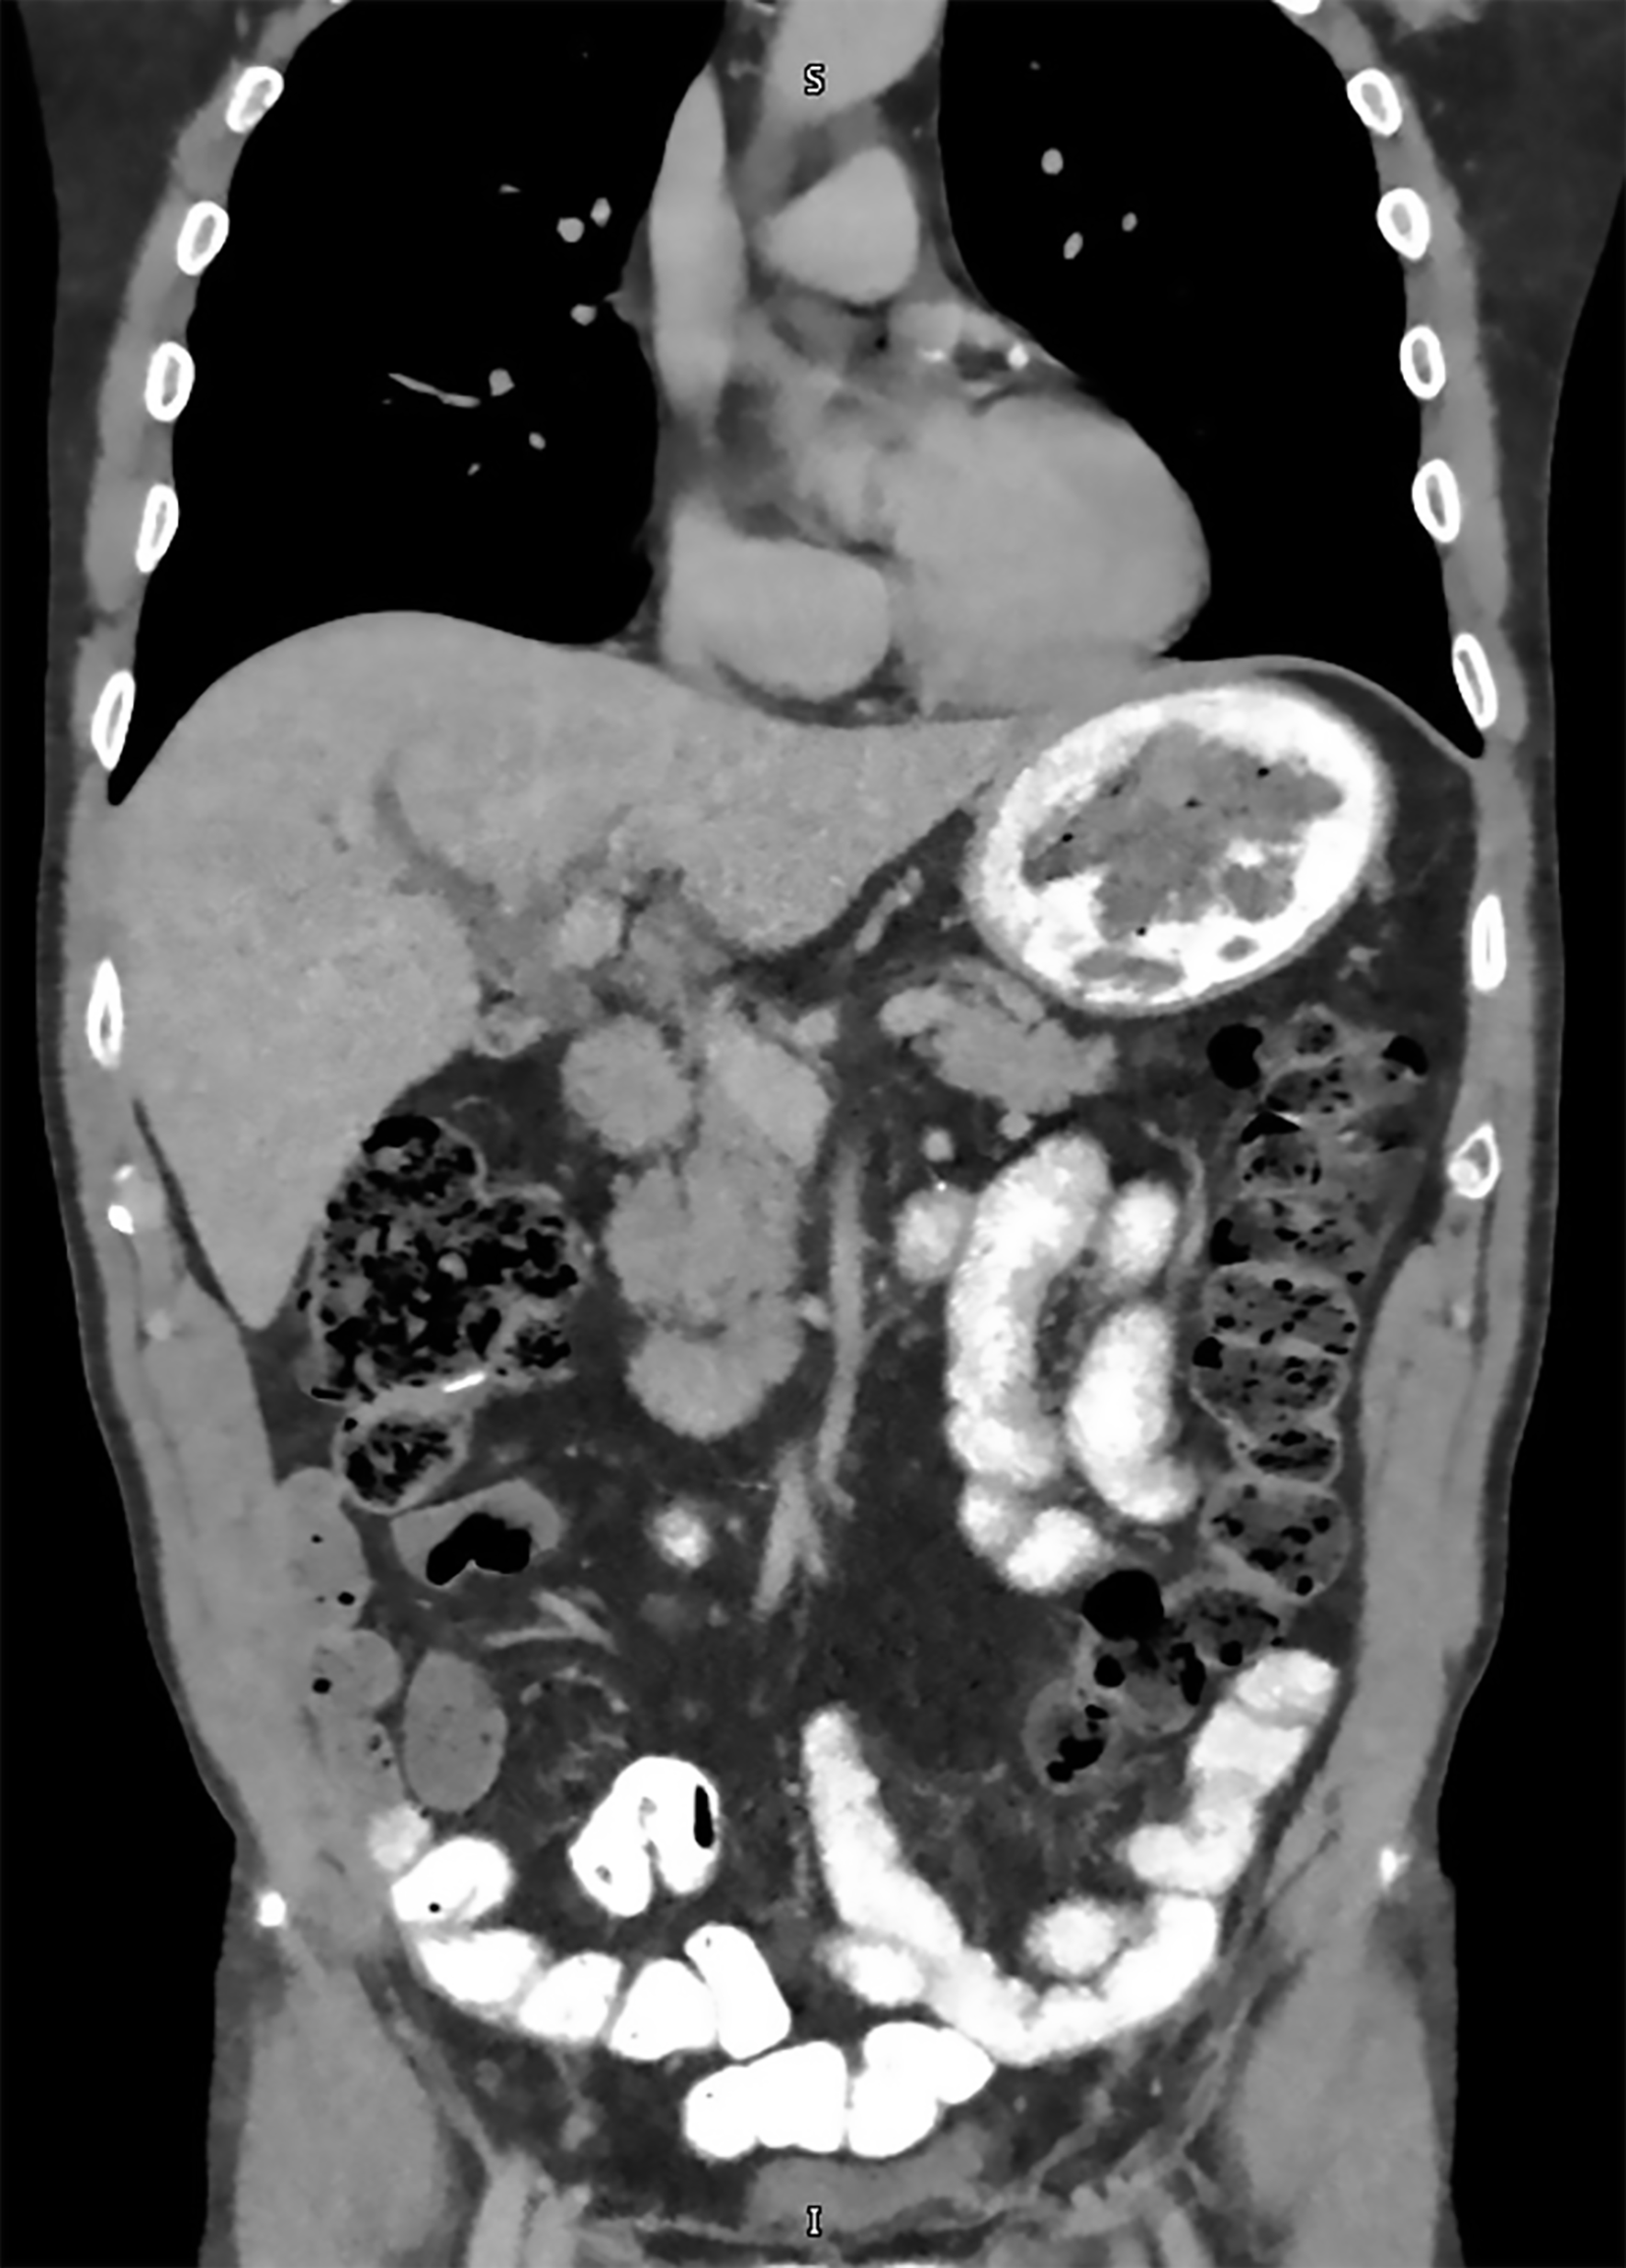

Imaging with computed tomography (CT) abdomen revealed severe intrahepatic bile duct dilatation with suspected abnormality at the level of the common hepatic duct (Figure 1). The distal common bile duct was normal in caliber. Magnetic resonance imaging (MRI)/magnetic resonance cholangiopancreatography (MRCP) showed intrahepatic biliary duct dilatation with a soft tissue lesion seen at the hilum branch point between the right and left biliary system that measured at least 2.6 cm in length (Figure 2). No focal liver lesions were noted. About 6 months prior to this scam, CT scans of the chest, abdomen and pelvis revealed only a tiny 4 mm left lung base subpleural nodule which was unchanged compared to previous scans. The nature of the biliary obstruction was intraluminal in nature and for further evaluation and biliary decompression, options were discussed as to the route for decompression. An endoscopic retrograde cholangiopancreatography (ERCP) was discussed vs options such as external drainage approach and patient opted for an external drain with interventional radiology as he feared potential complications of ERCP. Interventional radiology team placed an external biliary drain and obtained cytology samples simultaneously. The pathology results showed adenocarcinoma that favored a colorectal source of origin. Immunohistochemical studies demonstrated the tumor cells to be positive for cytokeratin (CK) 20 and caudal-type homeobox 2 (CDX2), and negative for CK7 (Figure 3).

A positron emission tomography-CT (PET-CT) scan was performed after discharge that revealed no definitive fluorodeoxyglucose PET/CT evidence of malignancy. There was no abnormal activity elsewhere including the bowel and prior surgical sites and no lymphadenopathy was noted (Figure 4). Mucinous implants to the hilum from colorectal malignancy could have been a possible differential in this case given the presentation. However, there was no evidence of any ascites or features of peritoneal carcinomatosis on any of the imaging studies he underwent.